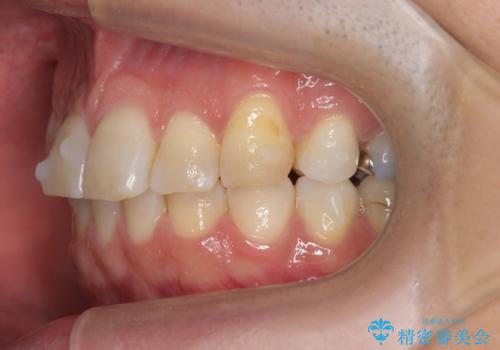

上の前歯が斜めに見えること、犬歯と小臼歯の間の隙間、上下顎前歯のがたつきを治すことをご希望されていました。

ご予算と患者様のご希望により、インビザライン・ライト(マウスピース14枚)によるマウスピース矯正を行いました。